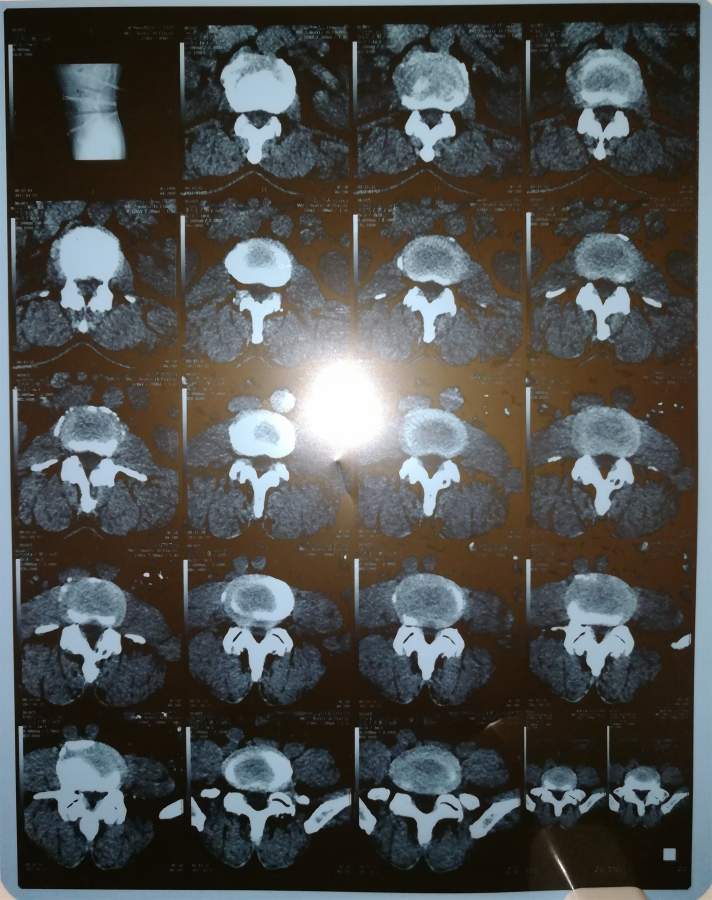

烦请论坛里的同志们给看下脊椎影像,谢谢谢谢已有2人参与